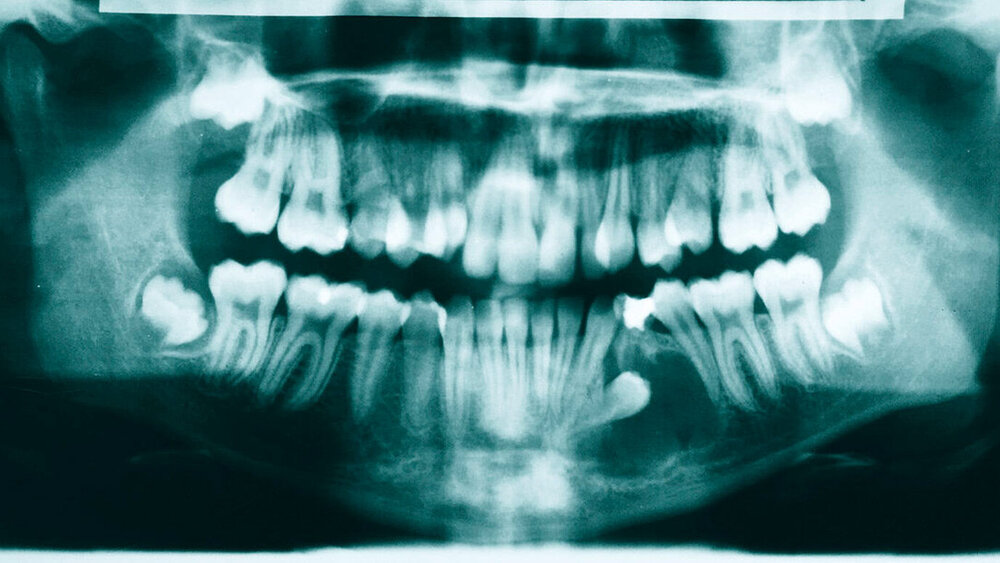

Klinisch zeigte sich extraoral eine seitengleiche Sensibilität und Motorik, die Nervenaustrittspunkte waren frei, die Mundöffnung war uneingeschränkt. Intraoral fand sich bei unauffälliger Mundschleimhaut ein vollständiges Erwachsenengebiss in Angle-Klasse I ohne Mittellinienverschiebung.

Zahn 25 befand sich im Durchbruch, Zahn 34 fehlte klinisch bei persistierendem Milchzahn 74. Zahn 23 stand in einer Kreuzbisssituation (Abbildungen 1 bis 3).

Im Orthopantomogramm imponierte eine Aufhellung, die sich regio 33 bis 35 nahezu über die gesamte vertikale Dimension des Unterkiefers erstreckte und die Krone des Zahnes 34 einschloss. Dieser lag horizontal verlagert, die Krone nach distal orientiert über die Wurzeln der Zähne 41 bis 74 projiziert. Zudem konnten die Anlagen der vier Weisheitszähne mit drohendem Engstand sowie ein nach mesial angulierter Zahn 24 befundet werden (Abbildung 4).